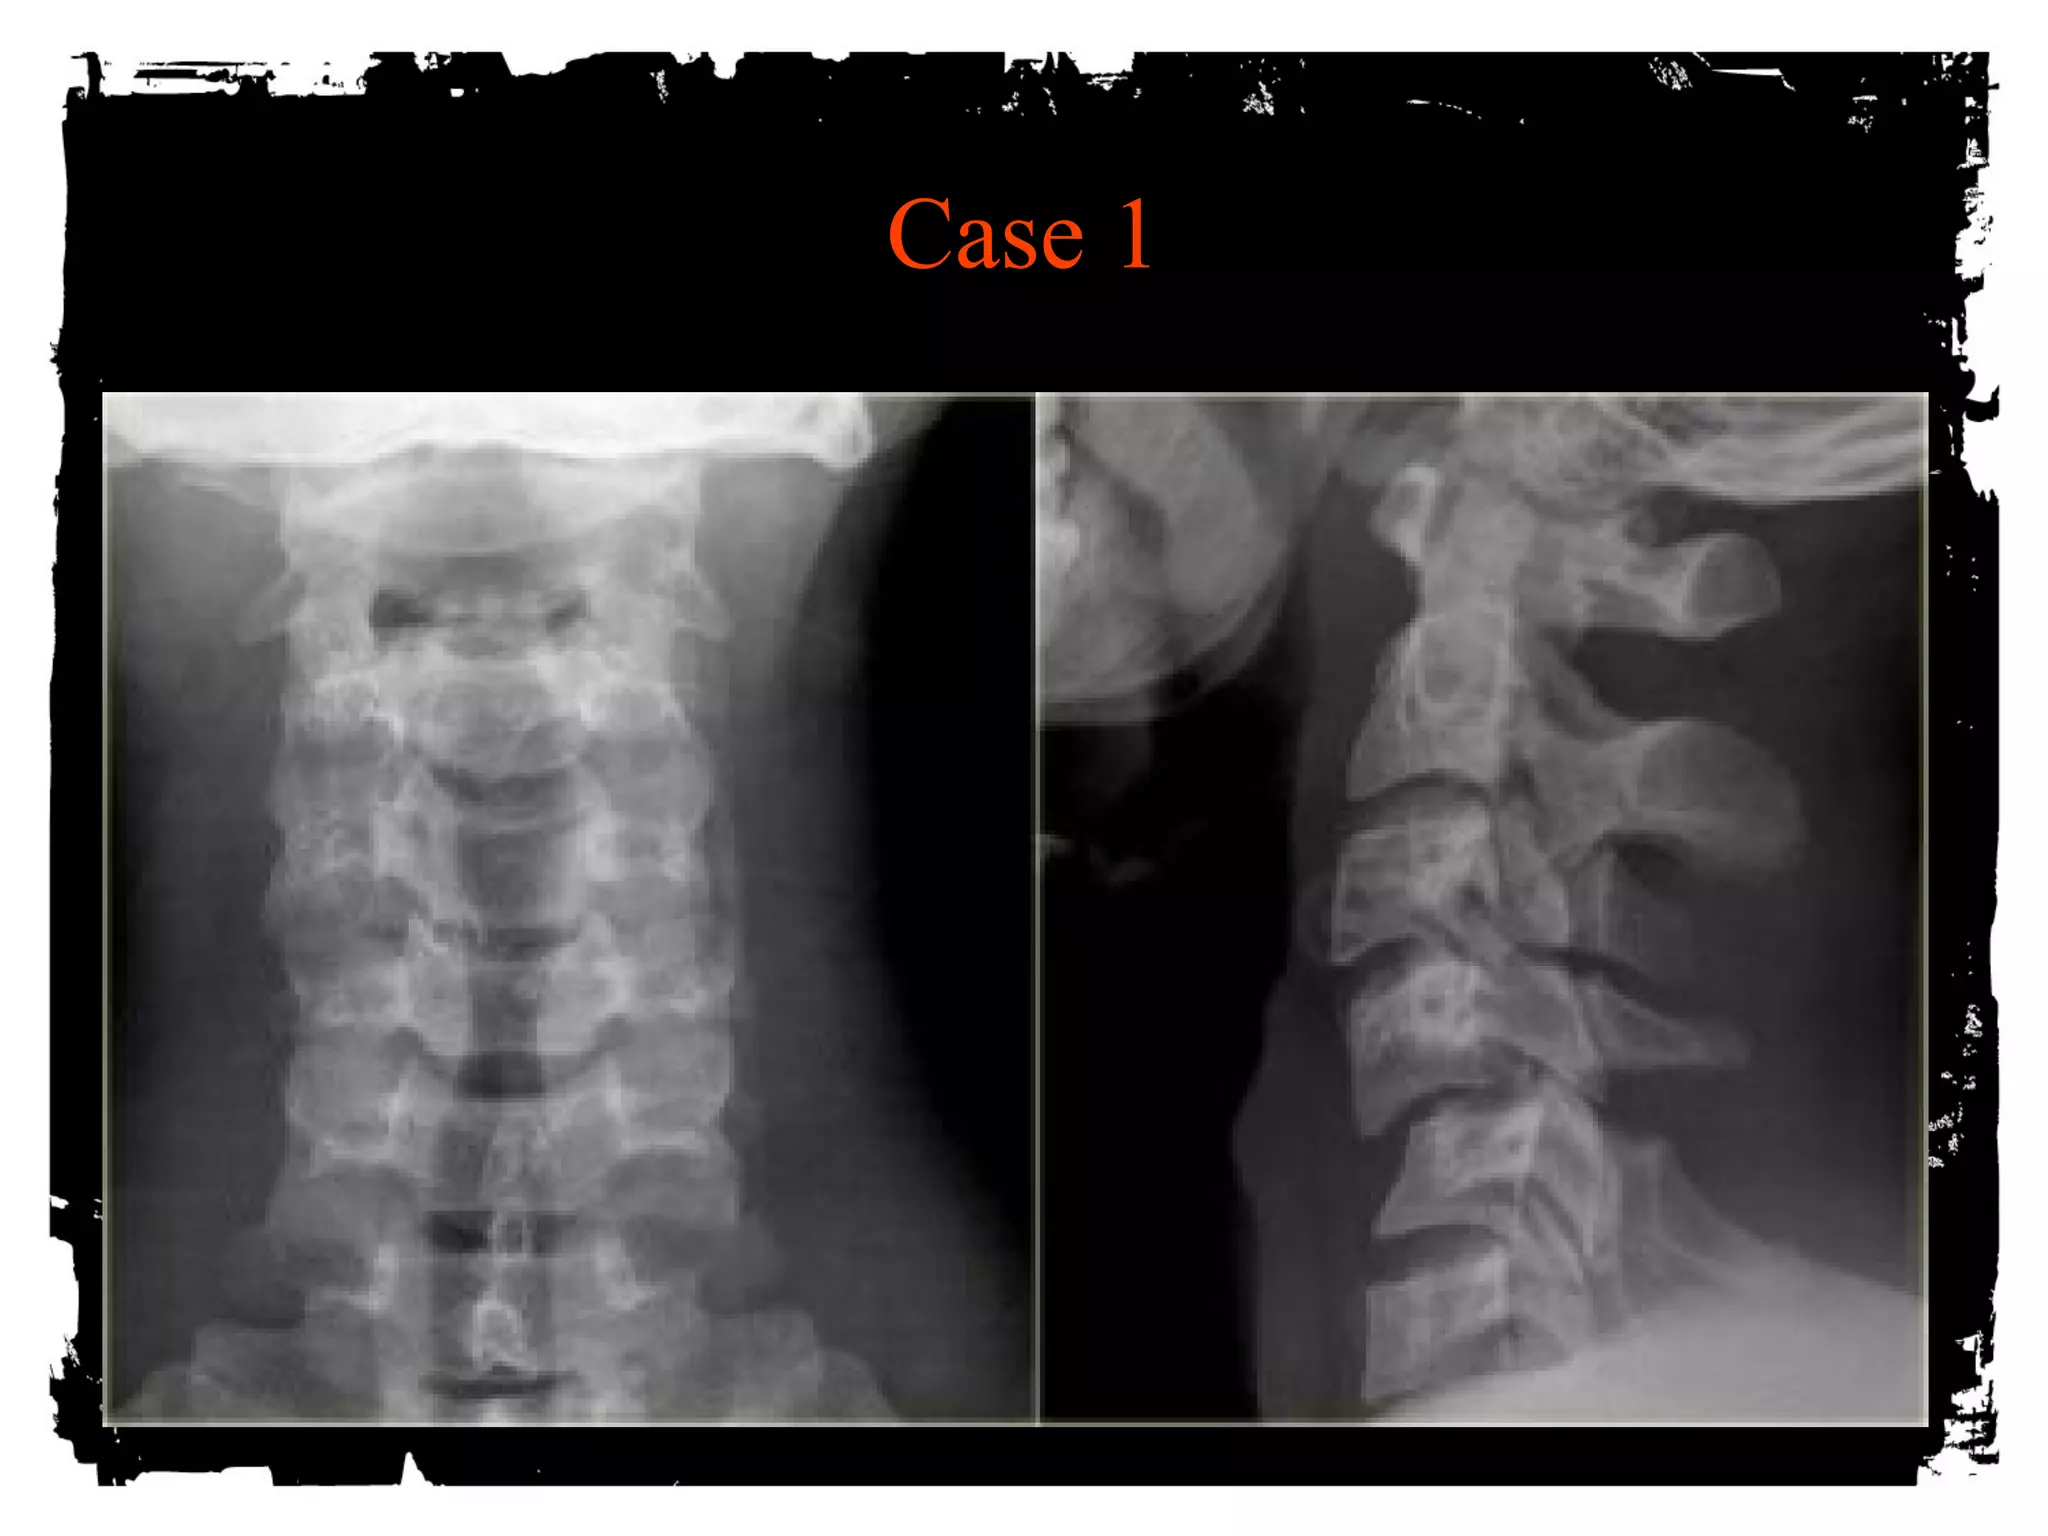

Case 1

CLICK HERE TO ADD TEXT

• Unilateral Facet Dislocation

Hyperflexion + rotation

Superior facet slides over inferior facet and becomes

locked

Anterior subluxation of superior vertebral body –25%

AP diameter

Stable injury

30% with associated neurologic deficit

MRI: disk extrusion leading to cord compression